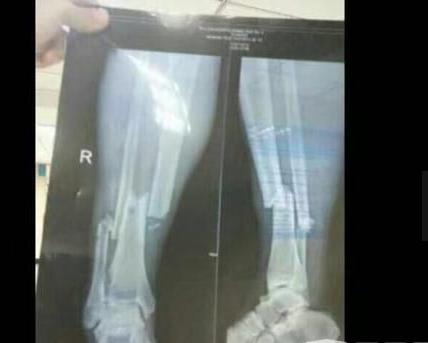

登巴巴断腿X光惨图

登巴巴断腿后一度疼的几乎晕厥,这个在赛场上就像猎豹的男人,疼的不停的哭泣呻吟。为了给他的腿复原,医生只能选择用麻醉药来让他感受不到疼痛,因为不麻醉他肯定是受不了的,甚至在整个康复期间,登巴巴也一度失望懊恼过,好在他都挺过来了。当时医生给他拍摄的X片,显示他的腿部已经粉碎性骨折非常严重,至今没有关于他腿部骨折的过多的图片视频,怕引起观众的不适感。